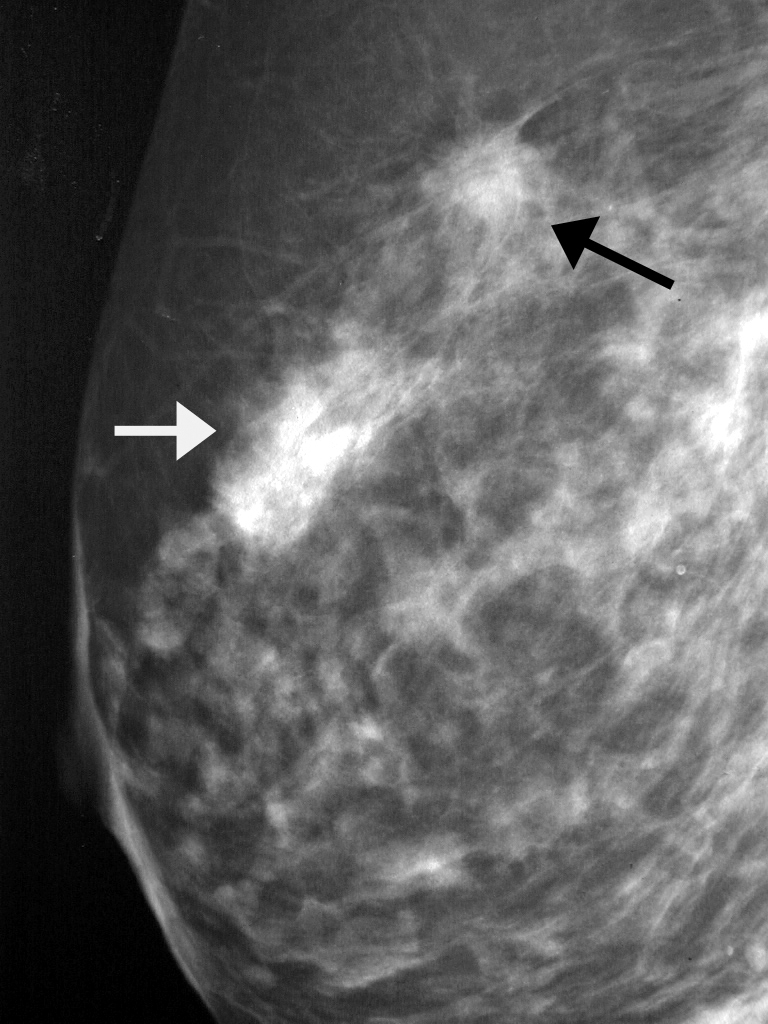

Что такое маммография: важность, процесс и результаты